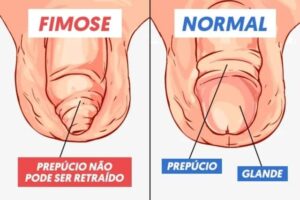

Entendendo os Graus de Fimose: Quando Procurar Ajuda Médica

A fimose é uma condição comum que afeta muitos homens, caracterizada pela dificuldade ou impossibilidade de retração do prepúcio sobre a glande (cabeça) do pênis. Embora possa ser uma condição